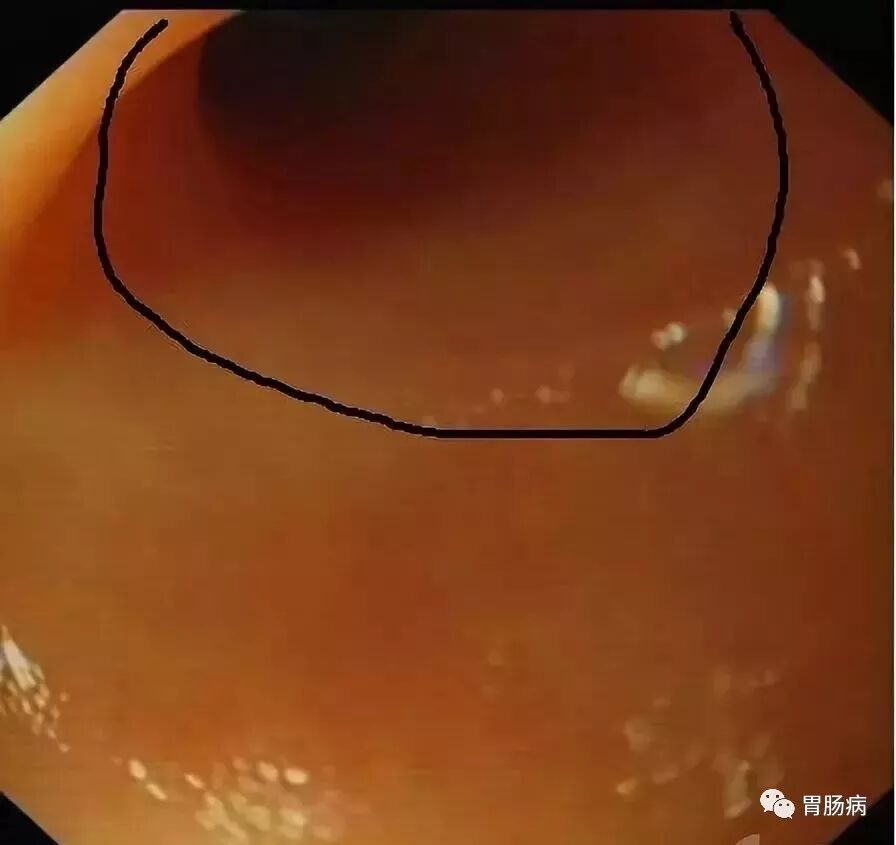

充分的肠道准备会有效减少ERAT操作时间,正常的阑尾开口部都被Gerlach’s瓣覆盖(如图,双箭头示Gerlach’s瓣);会造成插管困难,加上特制的锥形透明帽后插管就变得相对容易。

通过内镜前端的透明帽的帮助下,推开Gerlach’s瓣(黄箭头),并进行阑尾腔插管。